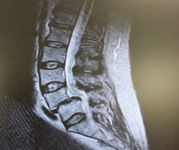

Spondylolisthesis

Spondylolisthesis & Minimally Invasive Transforminal Interbody Fusion